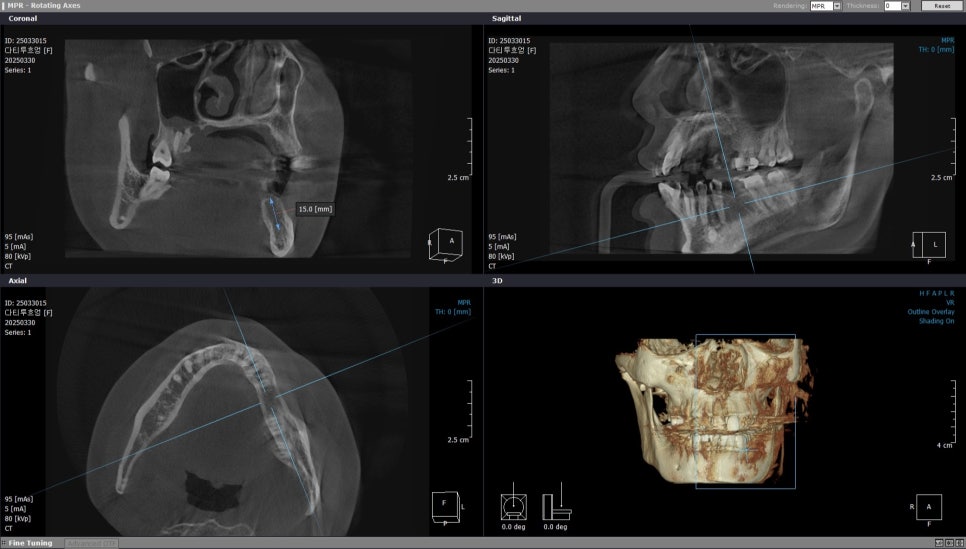

아래 왼쪽 첫번째 큰 어금니 부위

왼쪽 아래 첫번째 큰 어금니는

바로 인접한 치아가 앞쪽으로 기울어져

있는것을 확인 할 수 있었습니다.